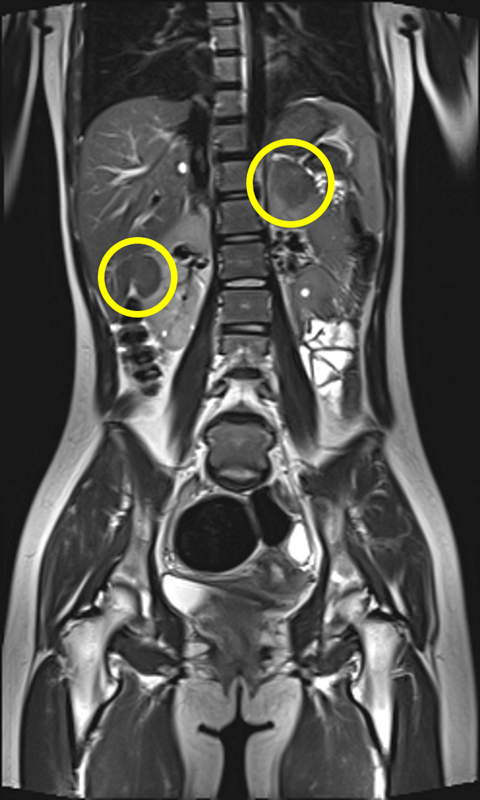

결절 경화증(tuberous sclerosis complex, TSC)은 종양억제유전자의 돌연변이로 인해 세포 증식이 조절되지 않고, 뇌·신장·피부·심장·폐 등 여러 장기에서 양성 종양이 발생하는 유전 희귀질환이다.

▲여러 장기에서 양성 종양이 발생하는 결절 경화증 환자의 복부 MRI 검사 사진. 양측 신장에 혈관근육지방종(노란색 표시)이 관찰되고 있다.

가장 흔한 증상인 뇌전증 발작과 피부의 혈관섬유종, 백반증을 비롯해 자폐스펙트럼장애, 인지장애, 신장 낭종, 폐세포 증식증 등 다양한 증상이 연령과 상관없이 나타나기 때문에 조기 진단과 장기적 관리가 필수적이다.